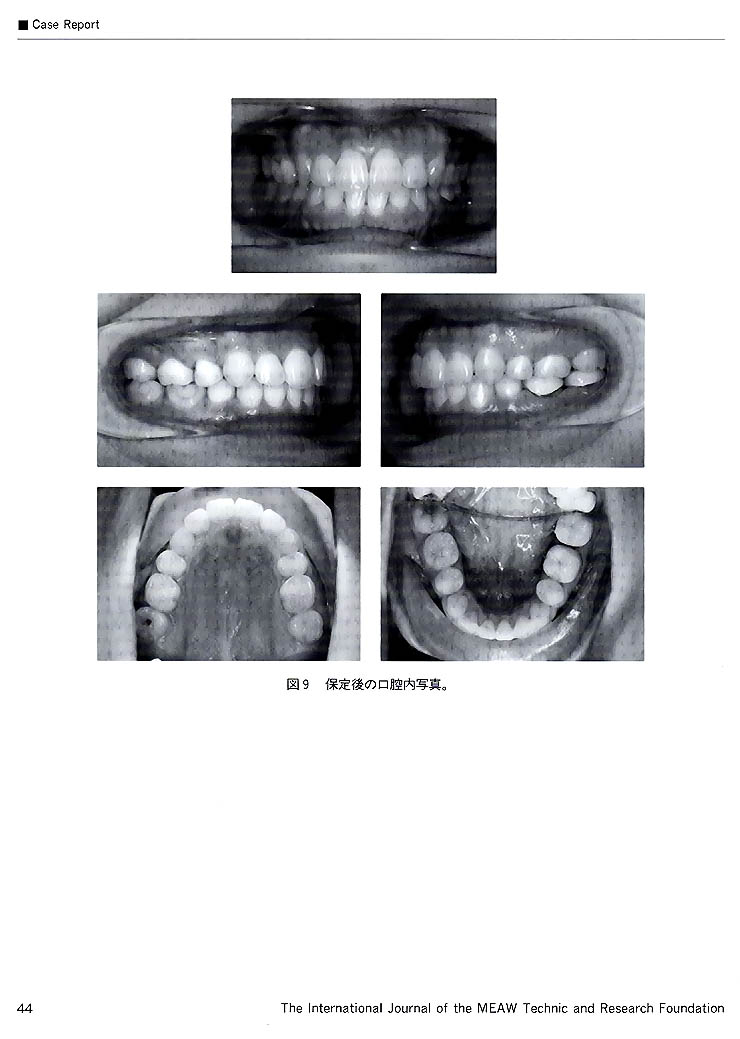

舌側からの矯正治療における MEAWの応用(和島)